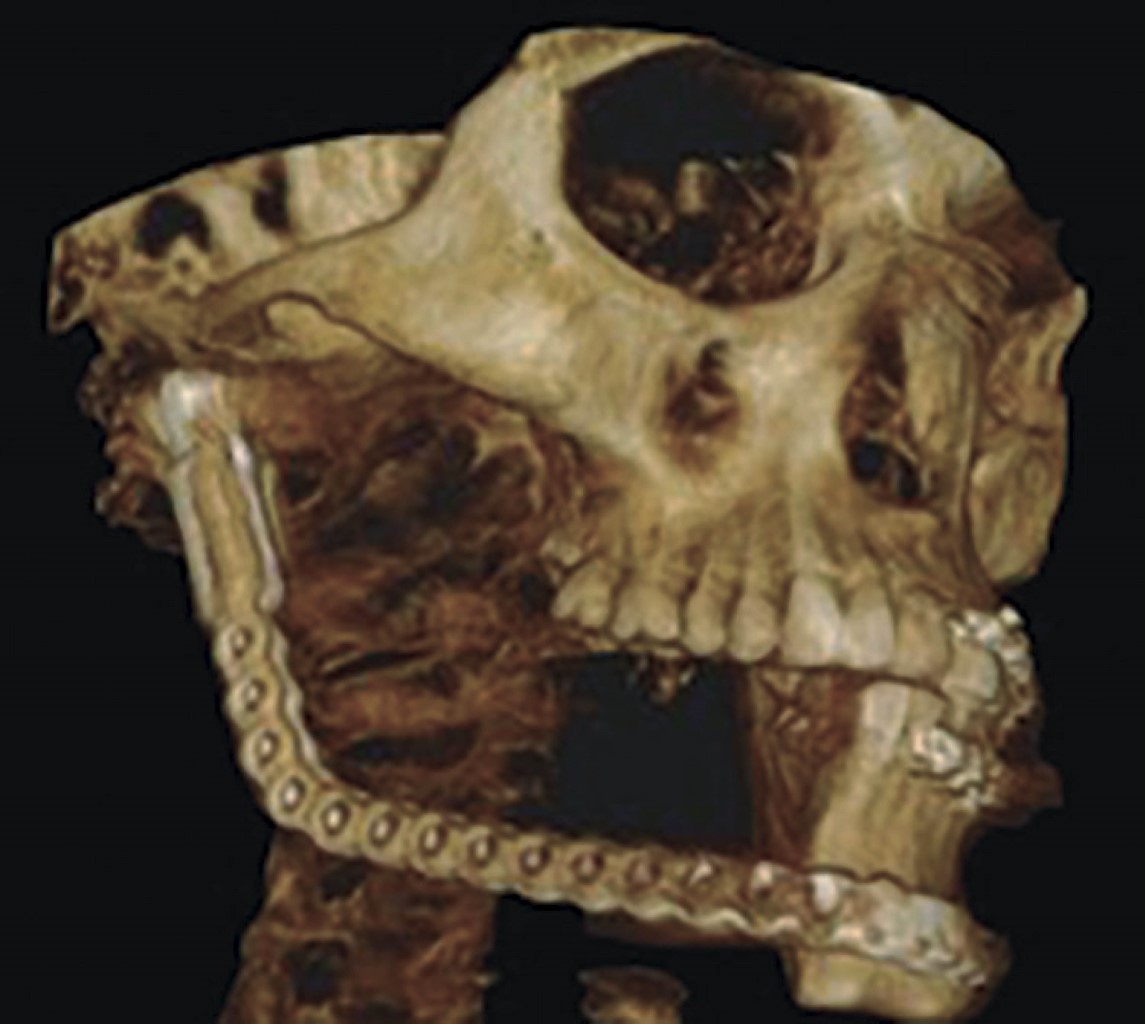

Se solicita tomografía helicoidal con cortes finos para la realización de modelo estereolitográfico (Figura 2A), donde se planean los márgenes quirúrgicos y se realiza precontorneado meticuloso de la placa de reconstrucción (Figura 2B).

Se solicita estudio de tomografía tipo cone beam postoperatoria inmediata, donde se aprecian márgenes quirúrgicos libres de lesión, así como material de reconstrucción en adecuada posición y función (Figura 4). Continúa la vigilancia postquirúrgica por consulta externa durante seis meses (Figura 5) y se corrobora diagnóstico y márgenes quirúrgicos con estudio histopatológico postoperatorio.

Figura 4